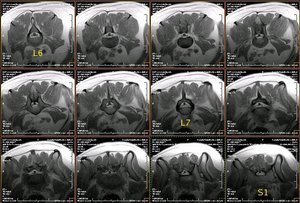

Resonancia magnética lumbo-sacra de pastor alemán |

La médula espinal acaba en L5, donde empieza la cola de caballo |